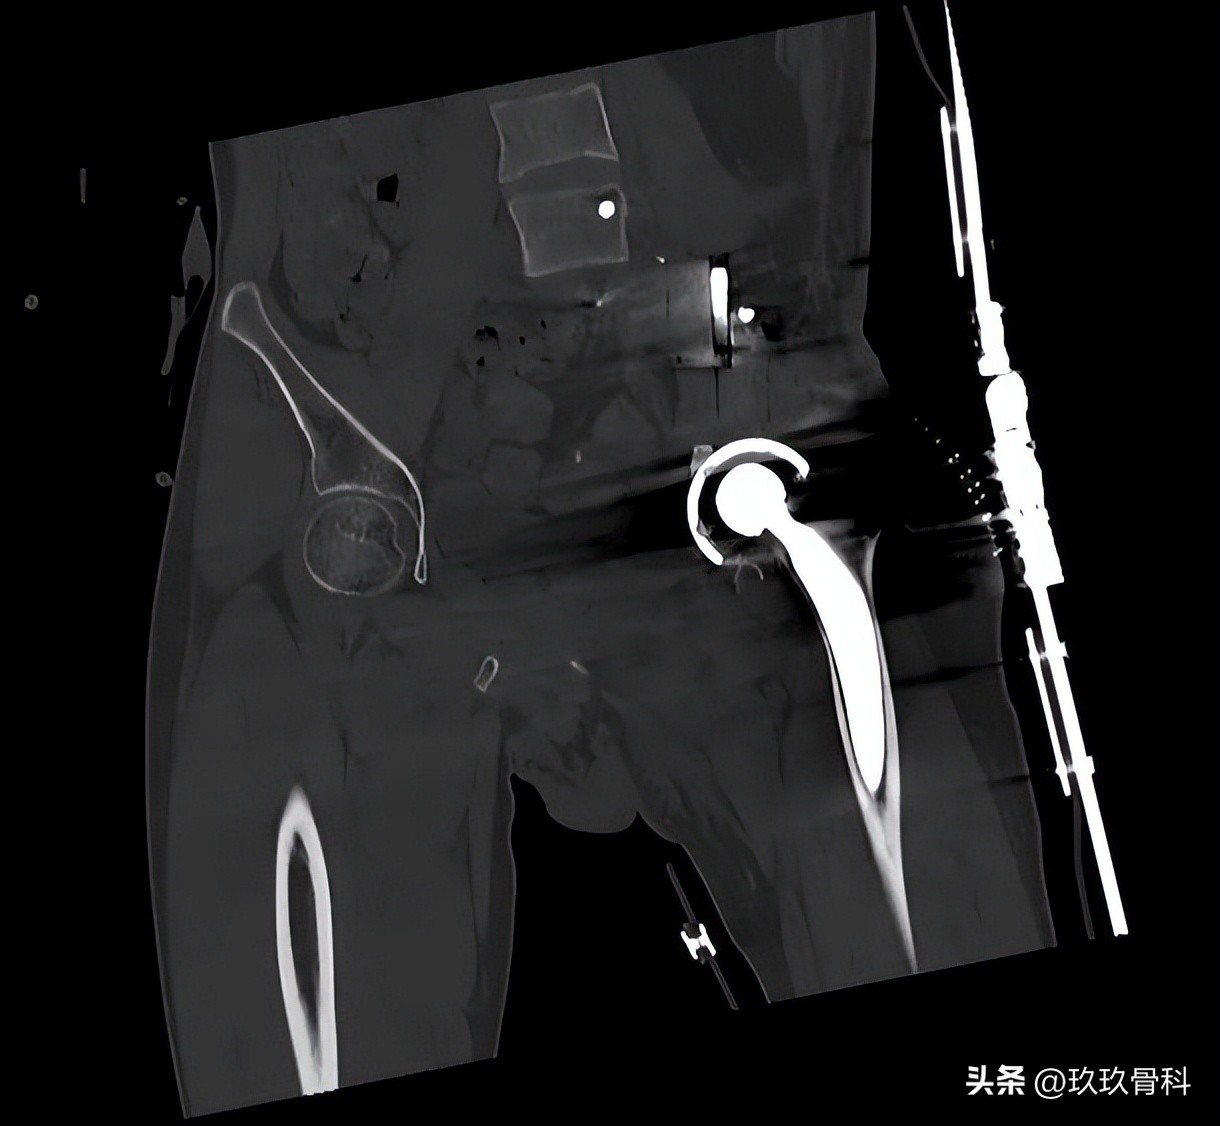

李浩淼主任为其完善相关检查后,确诊为左骨盆肿瘤切除术后半骨盆缺损,团队组织了多学科会诊,制定了完善的手术治疗方案,与力达康肿瘤团队设计了定制化假体假体,最终顺利开展手术,手术进展非常顺利。

术后影像